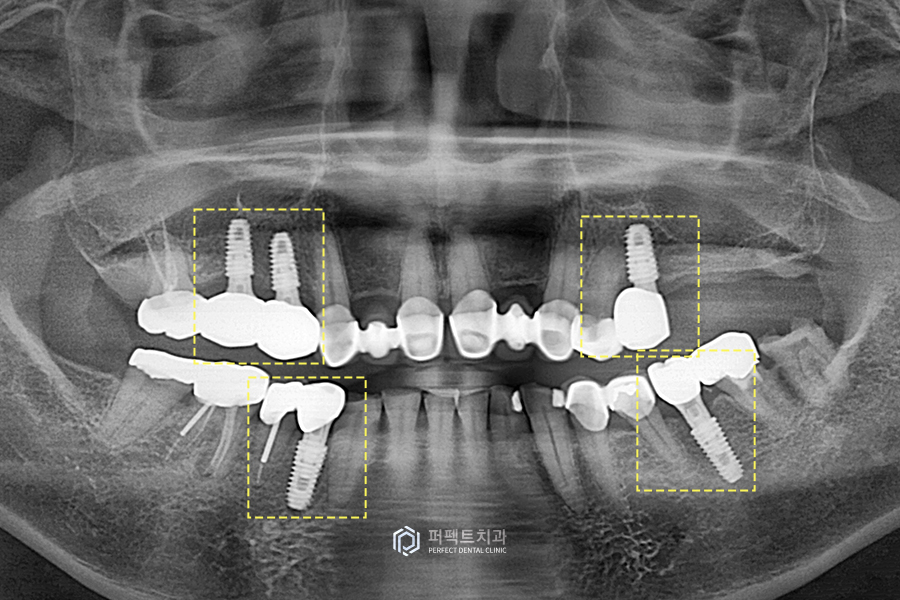

초진 파노라마 사진을 보시면 어금니가 많이 없는 것을 보실 수 있습니다. 그러다보니, 씹는 기능을 거의 앞니로만 하셨고 게다가 앞니 부분도 예전에 했던 보철물에 문제가 생겨서 앞니 보철을 교체하길 원하셨습니다.

윗니 사진을 보시면 어금니가 대부분 뿌리만 남아있거나 크라운이 벗겨져있어 제 기능을 못하는 상황이었습니다. 그리고 앞니 부분도 예전에 많이 사용했던 PFM크라운으로 치료가 되어있는데 이 부분도 깨져있고, 닳아있는 것을 볼 수 있습니다.